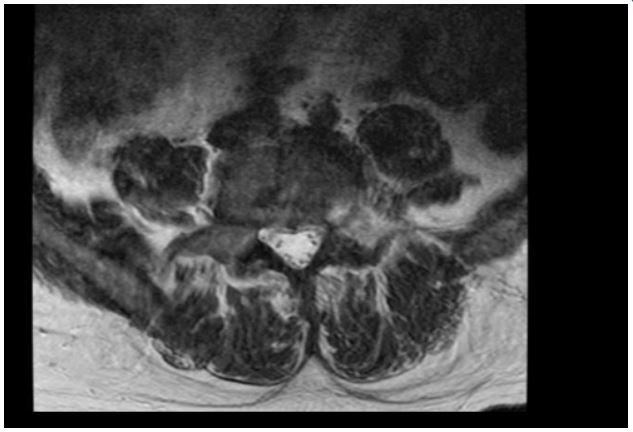

A 55-year-old man presented to an Internal Medicine physician after months of uncontrolled back pain despite of multiple therapies failure, asthenia, loss of weight and fever. Smoker, diagnosed of interstitial lung disease years ago, under follow-up by Pneumology and diagnostic doubts between bronchiolitis associated to tobacco smoking and pulmonary LCH, asymptomatic without specific treatment. Blood tests were unremarkable, with negative hepatitis serology and other infectious agents’ tests. Computer tomography of the chest showed centrilobular micronodules and cystic lesions in both lungs, with predilection for the mild and upper zones (Figure 1). These findings were consistent with the interstitial lung disease already known. A magnetic resonance of the spine showed multiple lytic bone lesions suggesting metastasis (Figure 2), so the study was completed with a PET scan that confirmed hypercaptation areas (Figure 3) in multiple vertebral bodies, scapula, pelvis, and costal arches.

Figure 1: Lung TC shows centrilobular micronodules and cystic with predilection for the mild and upper zones.